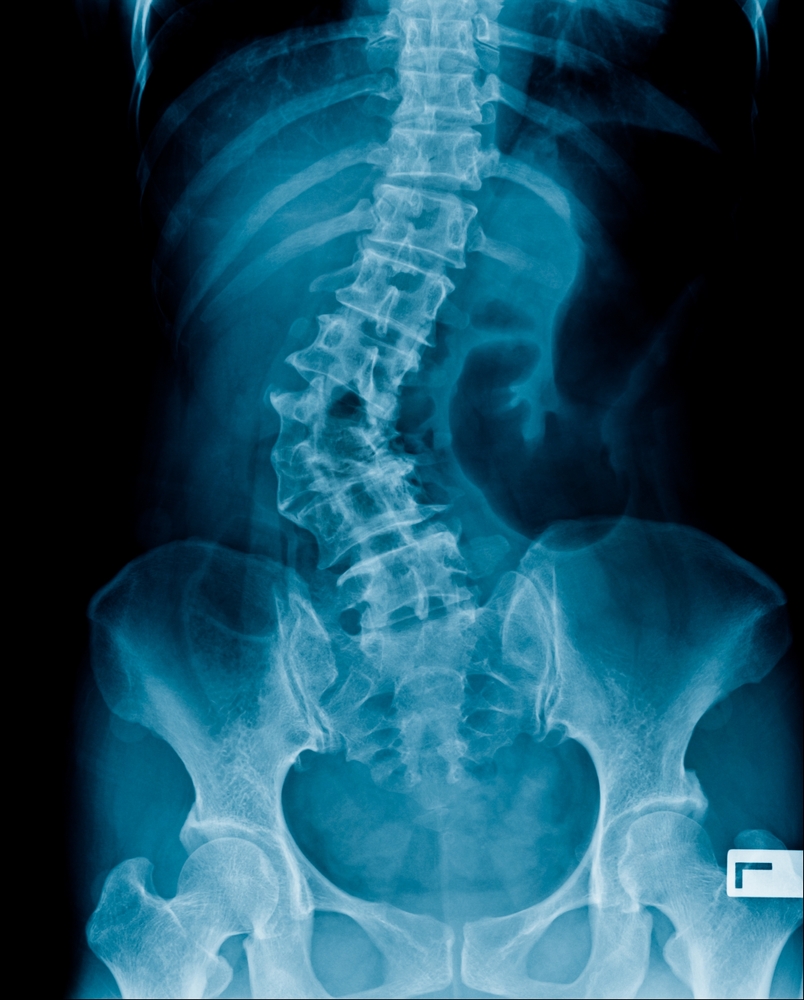

Esant reikalui, gydytojas gali paskirti papildomus tyrimus: rentgeno nuotraukas (dažniausiai iš priekio ir šono), kartais – magnetinio rezonanso arba kompiuterinės tomografijos tyrimus, kurie leidžia tiksliai įvertinti stuburo būklę.

Kaip matuojamas stuburo iškrypimas?

- Mažiau nei 10 laipsnių iškrypimas – neskaitomas kaip skoliozė

- Lengva forma – nuo 10 iki 24 laipsnių

- Vidutinė forma – nuo 25 iki 39 laipsnių

- Sunki forma – daugiau nei 40 laipsnių

Iškrypimo kampas matuojamas specialiu prietaisu – skoliometru, kuris uždedamas ant nugaros. Tikslesniam įvertinimui naudojamos rentgeno nuotraukos.